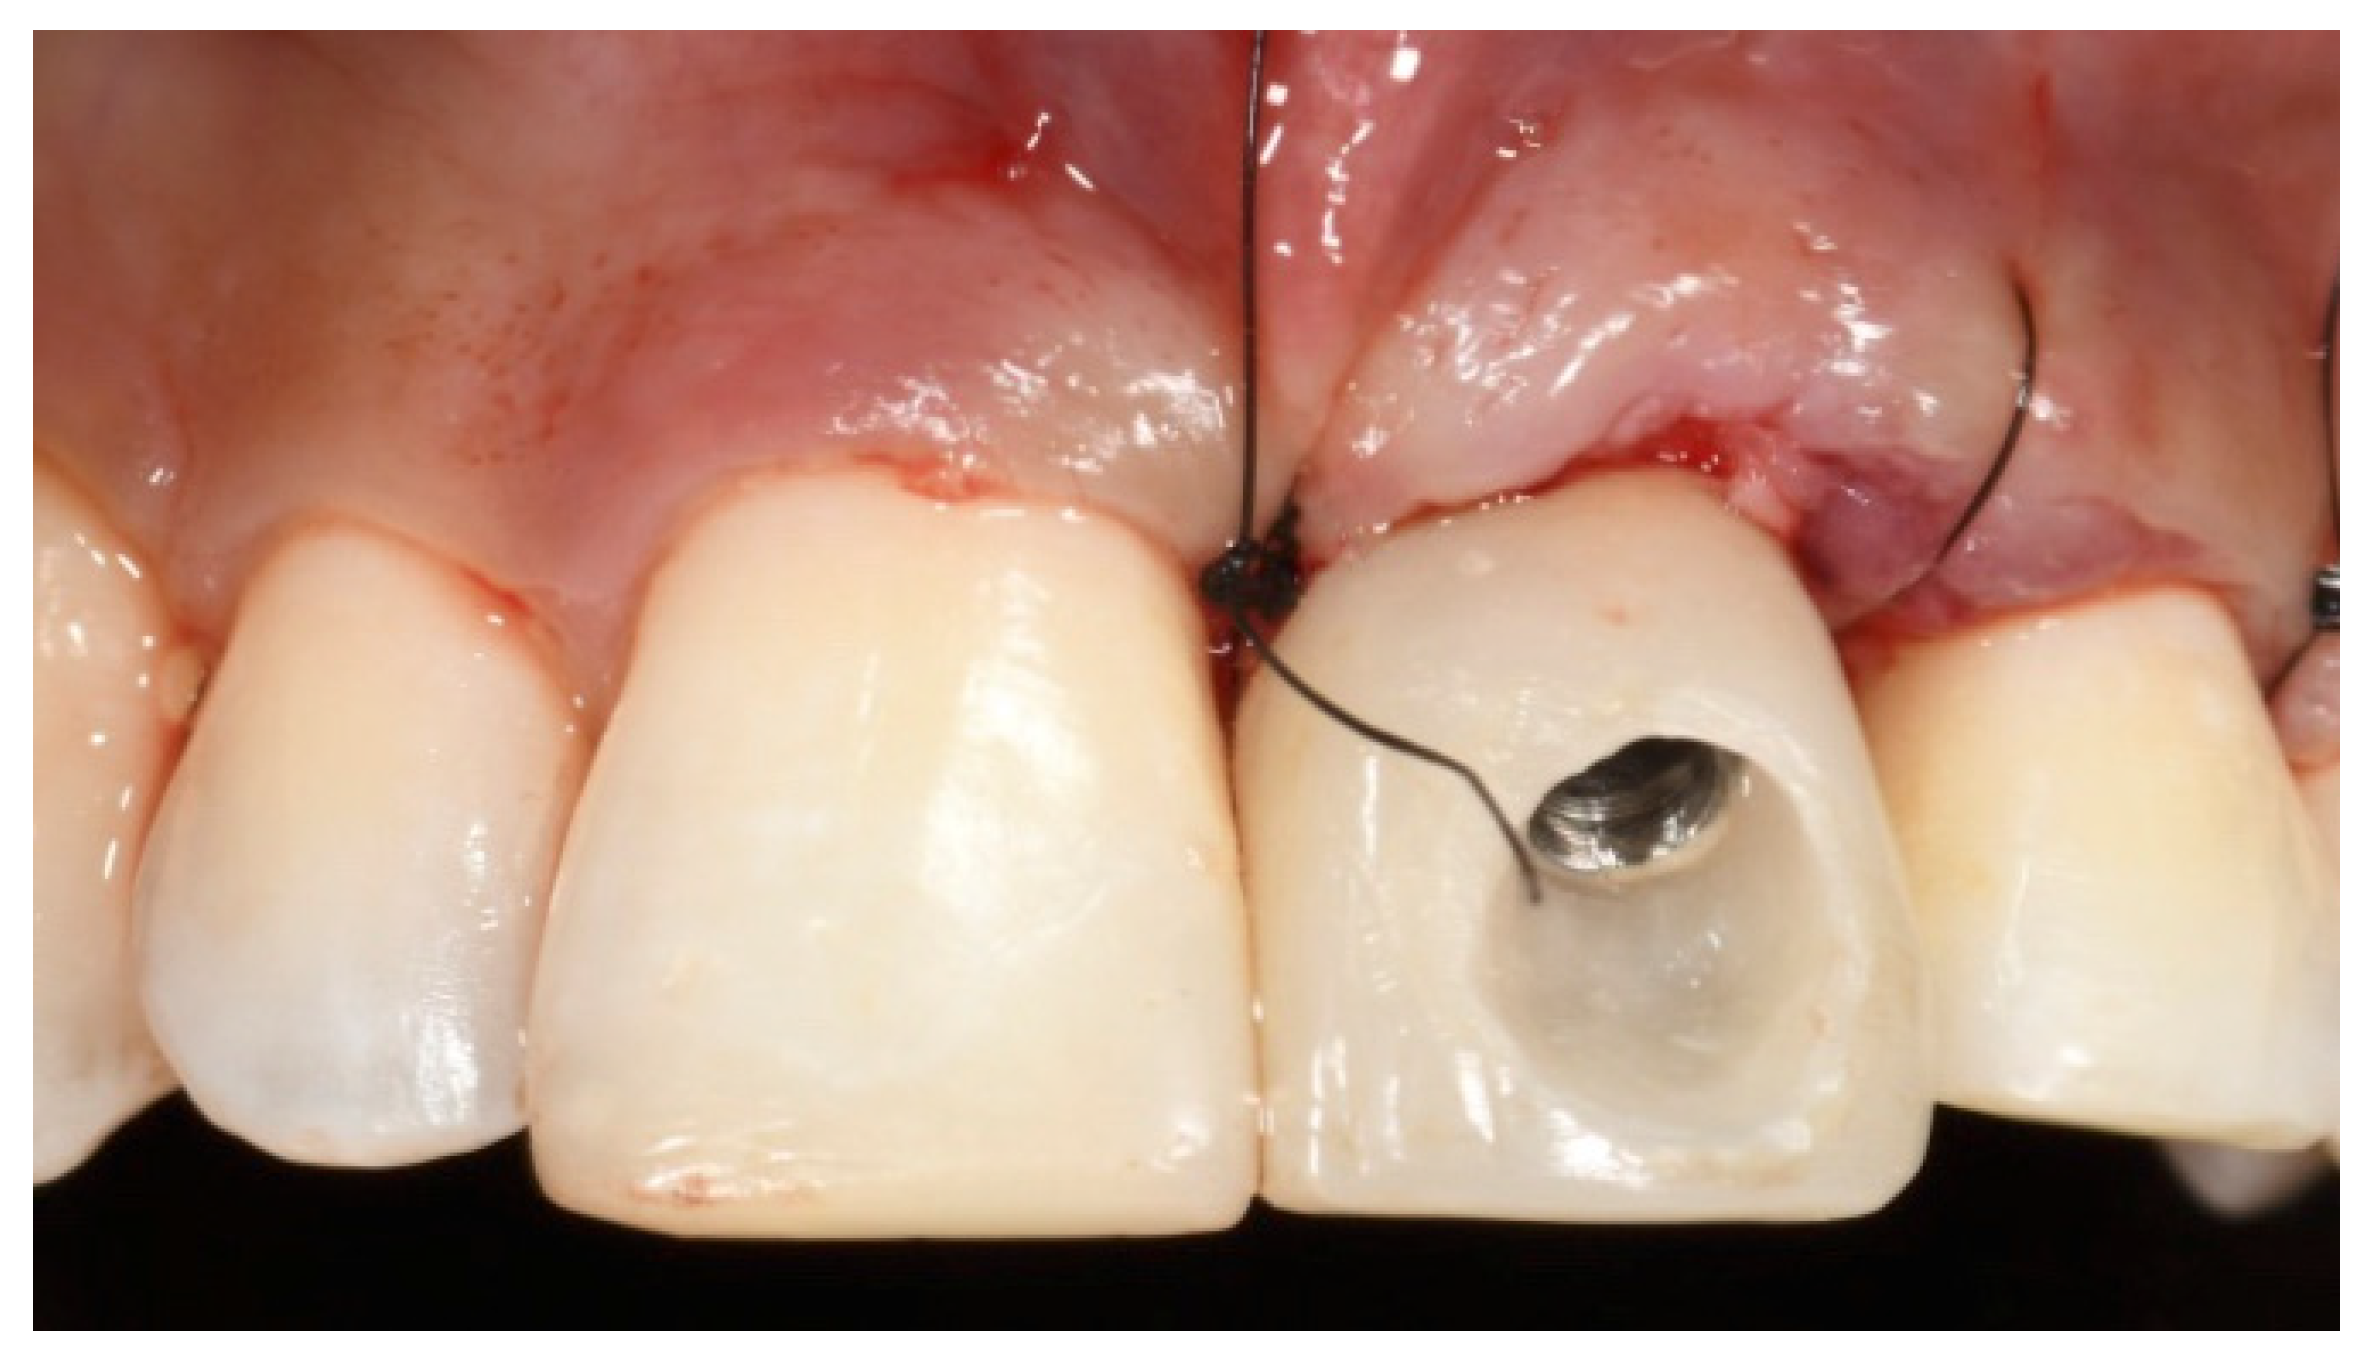

2. Case Presentation